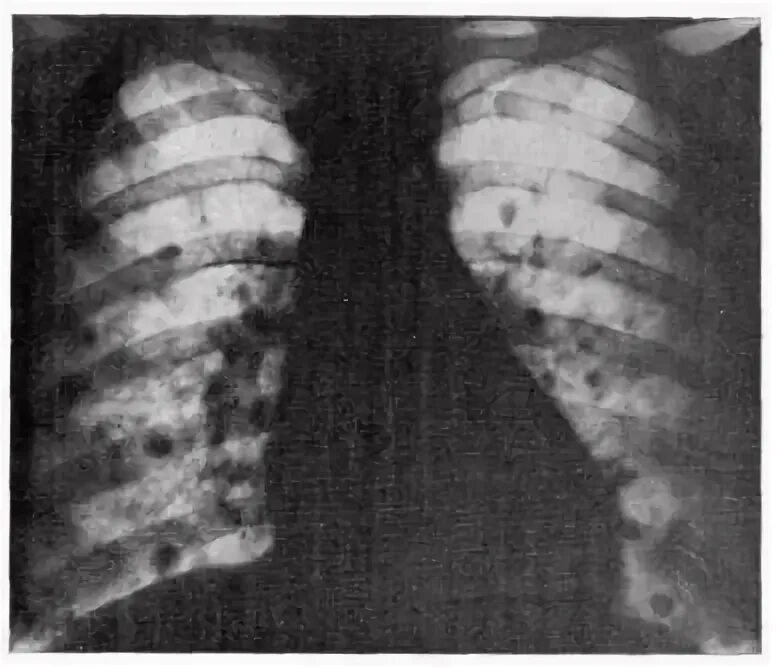

Единичные метастазы в легких